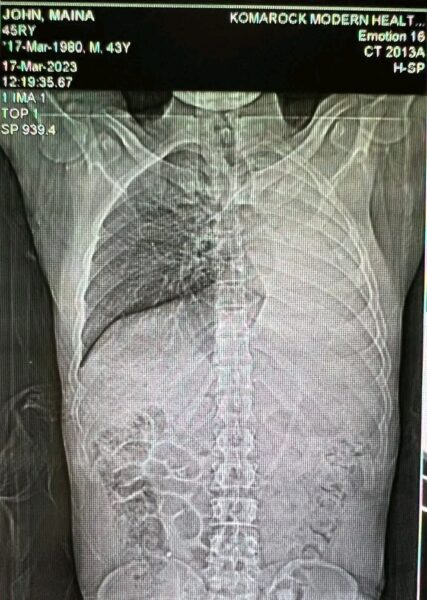

In 2021, the Nairobi-born reggae legend was diagnosed with pulmonary tuberculosis, which ultimately caused his left lung to collapse.

MC Fullstop’s left lung was severely compromised, a condition known as pneumothorax.

This occurs when air leaks into the space between the lung and chest wall, preventing the lung from expanding properly.

Symptoms include intense shortness of breath and chest pain. According to medical sources like Johns Hopkins, while people can survive with one lung, it places incredible strain on the body—especially if the remaining lung is also damaged.

“Hii imeenda” literally. My left lung has totally collapsed nimebaki na moja. In 2021 i was diagnosed with TB ya lungs ikasosi lungs kabisa. 2022 nikapata TB ya throat nayo ikanimaliza sauti, Running, walking, kuongea ni shida…….alafu lungs zina lungs ufala unlike Liver, haiwezi ji heal itabidi nijipange hapa naona niki hang boots. I just wanna say thanks kwa wale wamekuwa wakini support in this difficult moments God awa bless tu sana,” MC Fullstop wrote in March 2024.